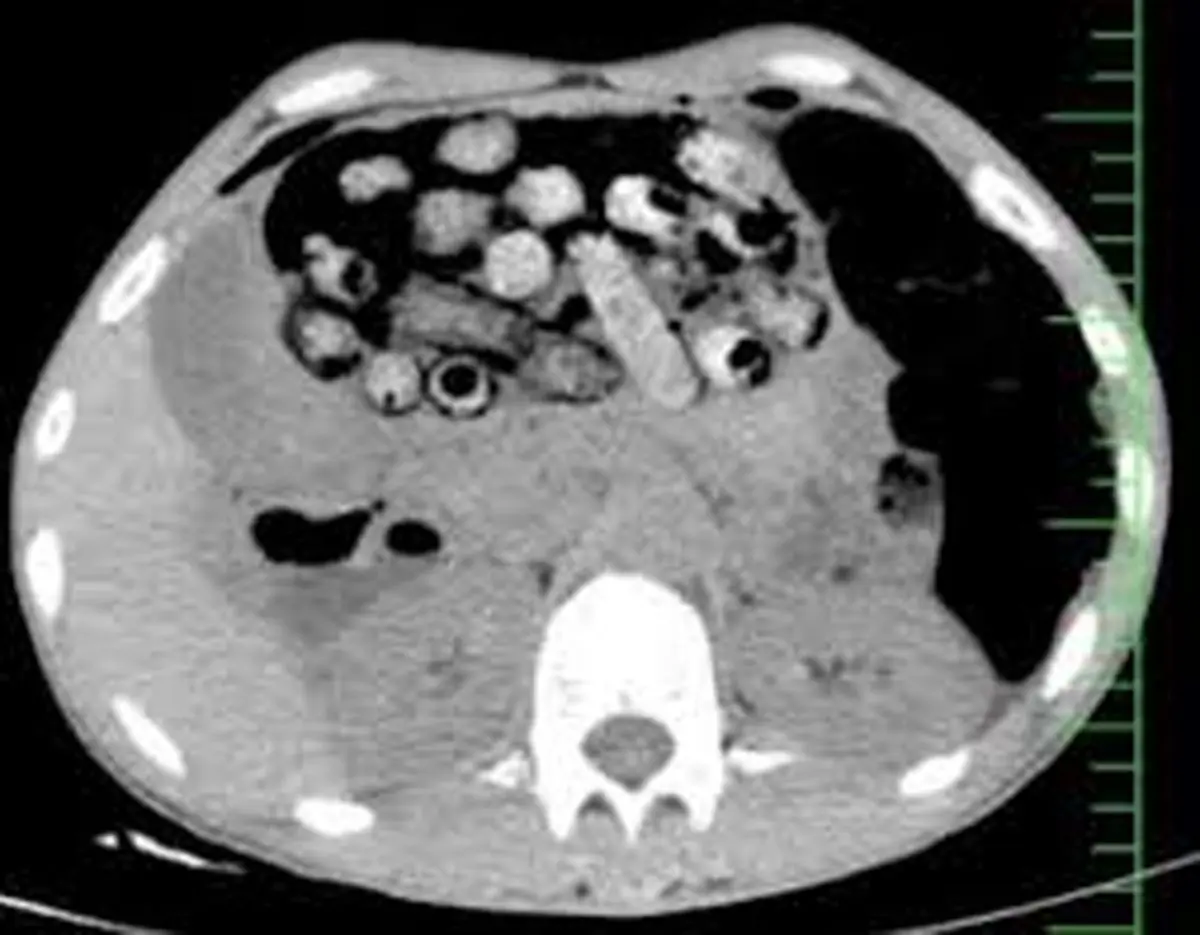

‌براساس اطلاعات اولیه مأمور همراه، بیمار پیش از مراجعه، اقدام به بلع تعدادی بسته محتوی مواد مخدر کرده بود. در پی انجام تصویربرداری فوری، تعداد زیادی بسته مشکوک در معده و روده کوچک و بزرگ وی مشاهده شد.

‌با توجه به خطر بالای پارگی احتمالی بسته‌ها و بروز عوارض تهدیدکننده حیات، بیمار بلافاصله به اتاق عمل منتقل شد و جراحی سنگین وی از ساعت سه بامداد آغاز شد.

‌در این جراحی که به سرپرستی دکتر سامان شیخی، عضو هیأت علمی گروه جراحی عمومی دانشگاه علوم پزشکی البرز و با همکاری تیم‌های اورژانس، تصویربرداری، بیهوشی و جراحی انجام و ۹۰ بسته از معده و روده بیمار خارج شد.